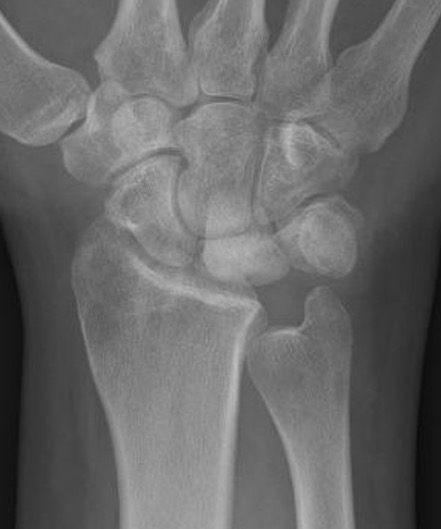

| Stage IIIB | Stage IV |

|

Collapse / fragmentation Scaphoid flexed / Capitate migrates proximally |

Pancarpal osteoarthritis |

![]() |